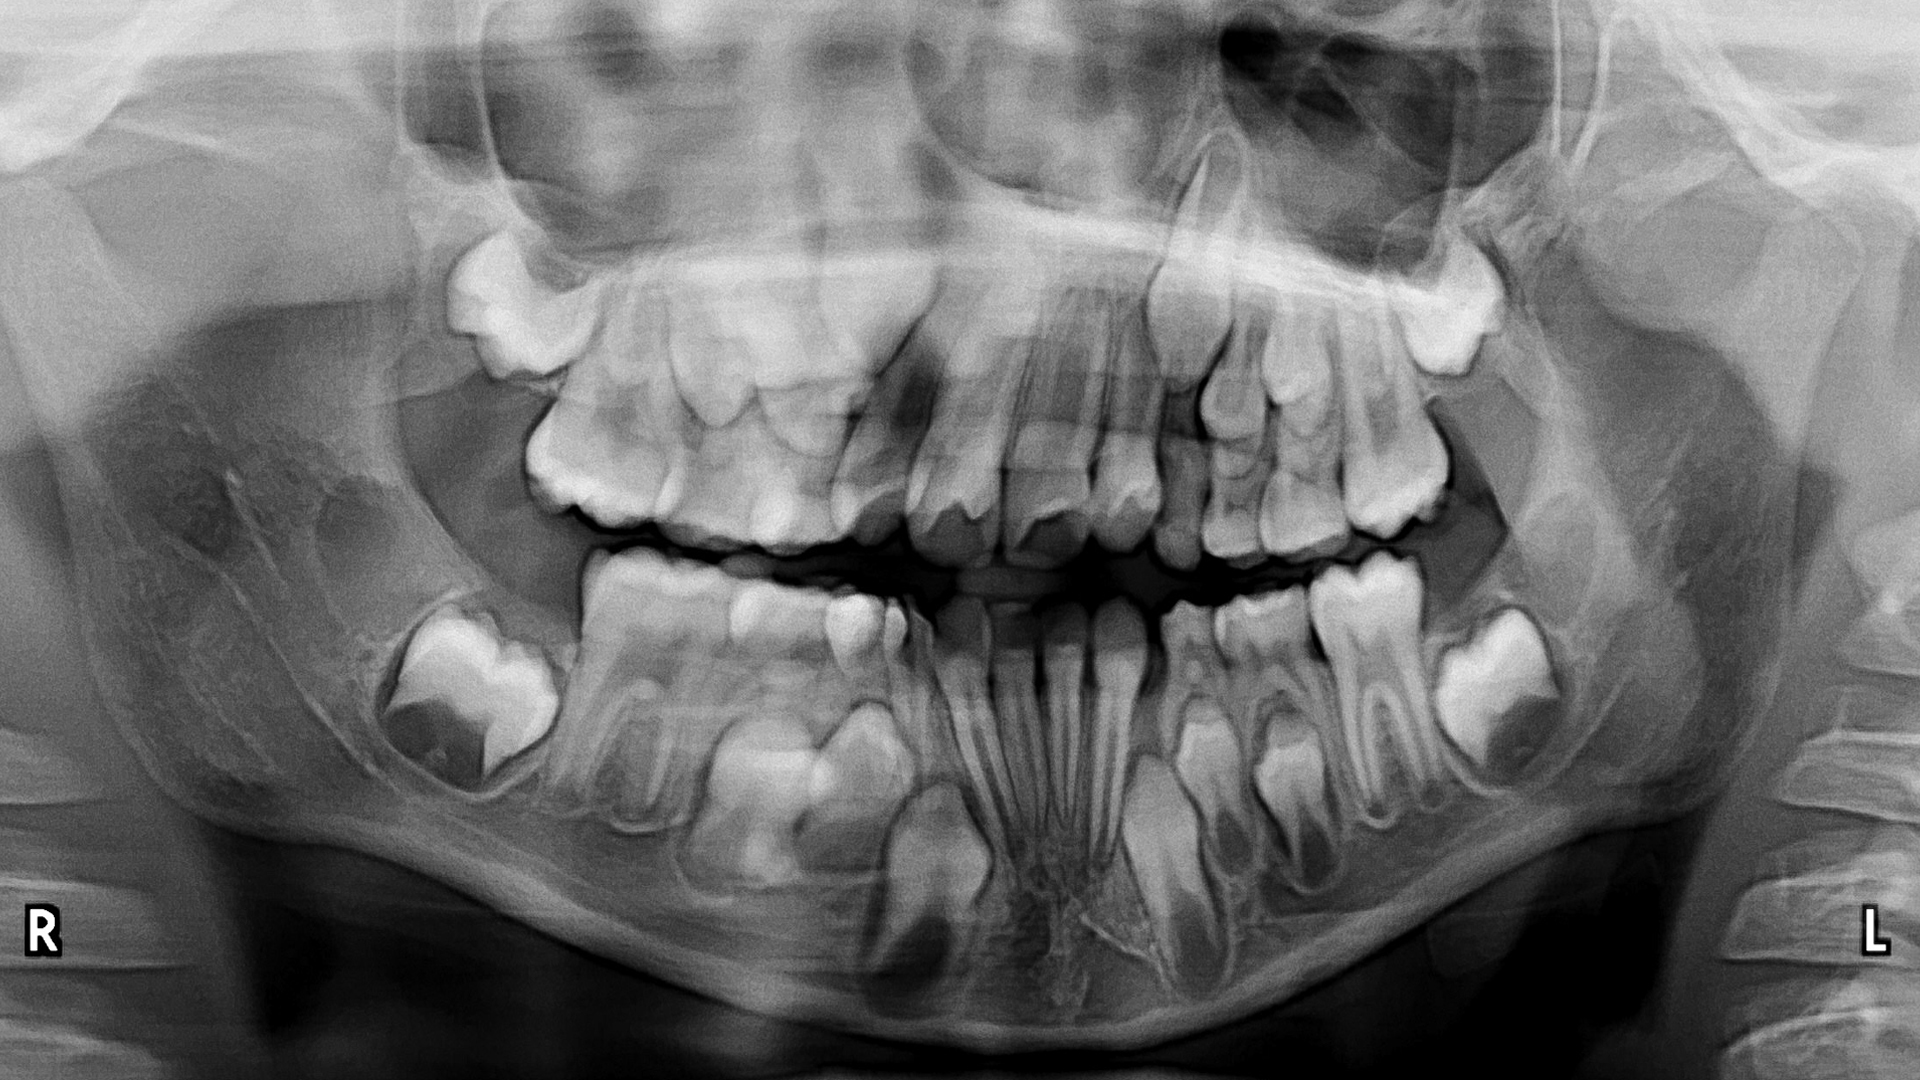

Recognizing the range of normal anatomical appearances on a well-made image is the most elementary step in image interpretation. At times, however, normal appearances can be altered as a result of patient anatomy, imaging system-related idiosyncrasies, or errors in patient positioning or image acquisition. Part 1 lecture will focus on panoramic image ordering practices, image acquisition and patient positioning, including positioning errors.

- how patient- and panoramic system-related factors can alter the appearances of normal anatomy.